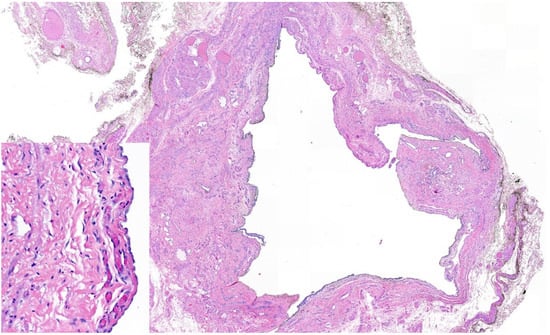

3. Case Report